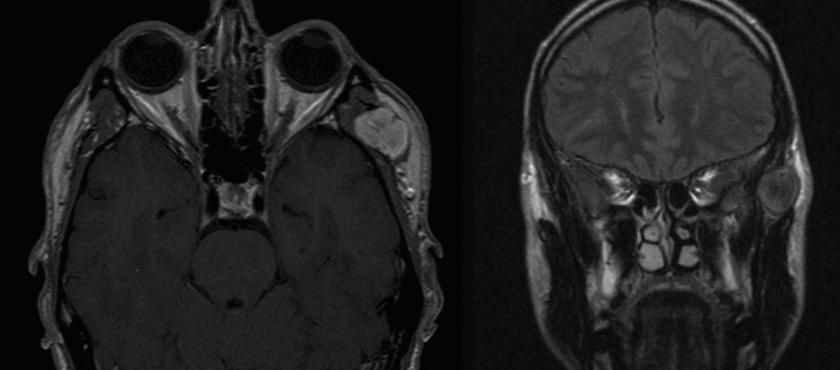

Eagle syndrome: Transient ischemic attack and subsequent carotid dissection

A 62-year-old man initially presented to our institution 3 months before his final diagnosis with transient right-sided weakness and brief loss of consciousness after reaching across his body in the shower. His medical history was significant for hypertrophic cardiomyopathy and atrial fibrillation. He had an implantable cardiac device and was on lifelong anticoagulation. Head computed tomography (CT) and CT angiography (CTA) were unremarkable, and although a transient ischemic attack (TIA) was thought to be unlikely given the anticoagulation therapy, this was a working diagnosis based on his symptoms, which were otherwise unexplained, and he was sent home.

The patient returned 3 months later with sudden-onset behavioral changes, disorganized speech, and right-sided weakness. He reported no specific activity related to symptoms. CTA demonstrated complete left internal carotid occlusion at the level of the styloid tip, 1-cm cranial to the bifurcation, which extended to the carotid terminus (figure 1). Review of imaging obtained at his presentation 3 months earlier demonstrated a normal carotid.

CT of the head obtained at the most recent visit demonstrated new anterior, middle, and posterior circulation infarcts. In addition, we observed not only that his left styloid process was elongated (3.0 cm), but also that his stylohyoid ligament was calcified to the hyoid and possibly fractured (figure 2). We speculate that the fracture might have acted as a lead-point, causing injury

and subsequent dissection of the patient’s carotid. The contralateral styloid process was within normal limits, but the ligament was also calcified.

Prophylactic contralateral styloidectomy was considered, but the patient was deemed a poor surgical candidate given his underlying cardiomyopathy and anticoagulation. After further review of imaging, we felt his right carotid was a safe distance from the right styloid and ligament. As the left carotid was occluded to the skull base, he was not offered revascularization. We speculate that our patient’s initial presentation

A B

Figure 1. A: 3-D reconstruction of the patient’s CTA with soft-tissue subtraction demonstrates the elongated and calcified stylohyoid ligament and dissected carotid artery cranial to the ligament (arrow). B: Additional 3-D reconstruction of the CTA with bone and soft tissue removed further demonstrates the dissected left internal carotid artery (arrow).

might have been a harbinger of his impending cerebrovascular accident.

Eagle Syndrome is an uncommon but well-described entity with a nonspecific clinical presentation; more benign manifestations include globus sensation, dysphagia, facial neuralgias, throat pain, and cranial neuropathies, for which a differential is extensive.1,2 In the presence of an elongated styloid bone or stylohyoid, diagnostic consideration is often given to Eagle syndrome, but it may have a more insidious presentation. Elongation of the styloid also has been reported as a cause for symptomatic carotid disease, including TIA, Horner syndrome, eye pain, and cluster headache.3 Dissection associated with elongated styloids has been reported in the neurology literature,4 but to the best of our knowledge, no prior reports have demonstrated TIA with a normal carotid and subsequent carotid dissection during two separate clinical presentations.

Surgical and nonsurgical treatments for Eagle syndrome have been reported. Medical treatments, including carbamazepine, local and systemic steroids, and NSAIDS have been used.4 Surgical options include transpharyngeal resection, as originally favored by Eagle, versus an extraoral resection.